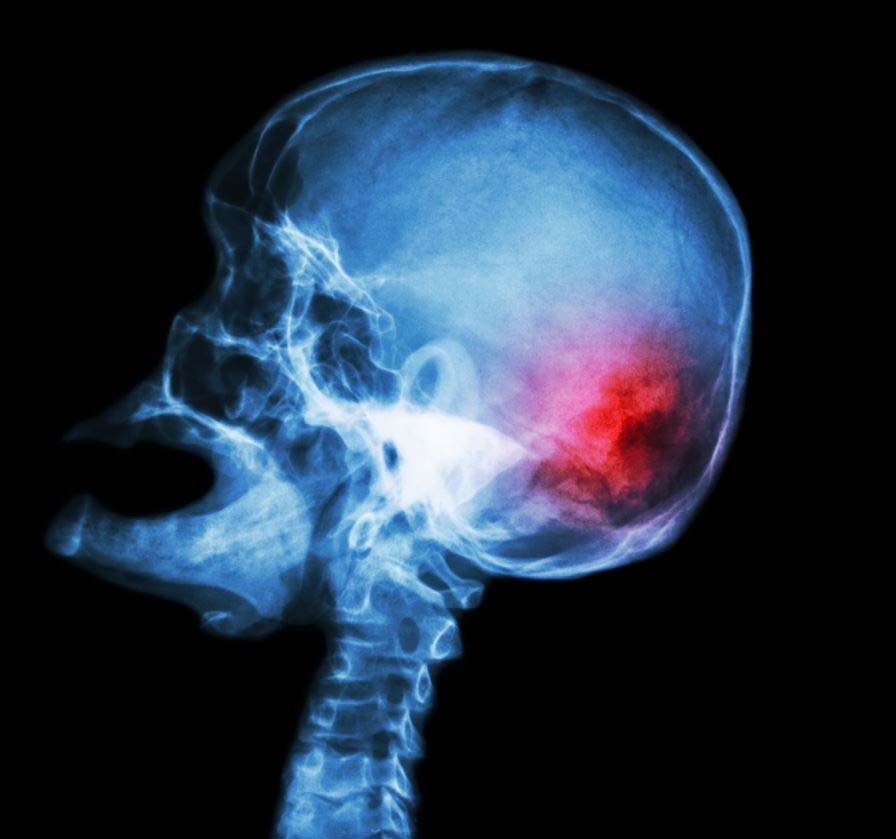

Мигрень и инсульт – это два частых, но гетерогенных нейроваскулярных заболевания со сложной связью.

✔️Мигрень с аурой характеризуется низким порогом головного мозга для корковой распространяющейся депрессии -биологический субстрат ауры, который может быть вызван многими факторами, в том числе специфическими заболеваниями, которые сами по себе могут увеличить риск ишемического инсульта.

✔️Эти исследования показывают, что мигрень увеличивает риск ИИ, однако нет четкой связи между ИИ и мигренью без ауры.

✔️В большинстве исследований, особенно с проспективным дизайном, прослеживается связь у пациентов с мигренью с аурой(МА), у таких пациентов риск удваивается.

✔️Появляется все больше доказательств того, что МА ассоциируется не только с ишемическим инсультом, но также с рядом других сосудистых заболеваний. Популяционное исследование среди женщин предполагает, что МА также относительно увеличивает риск геморрагического инсульта (относительный риск)